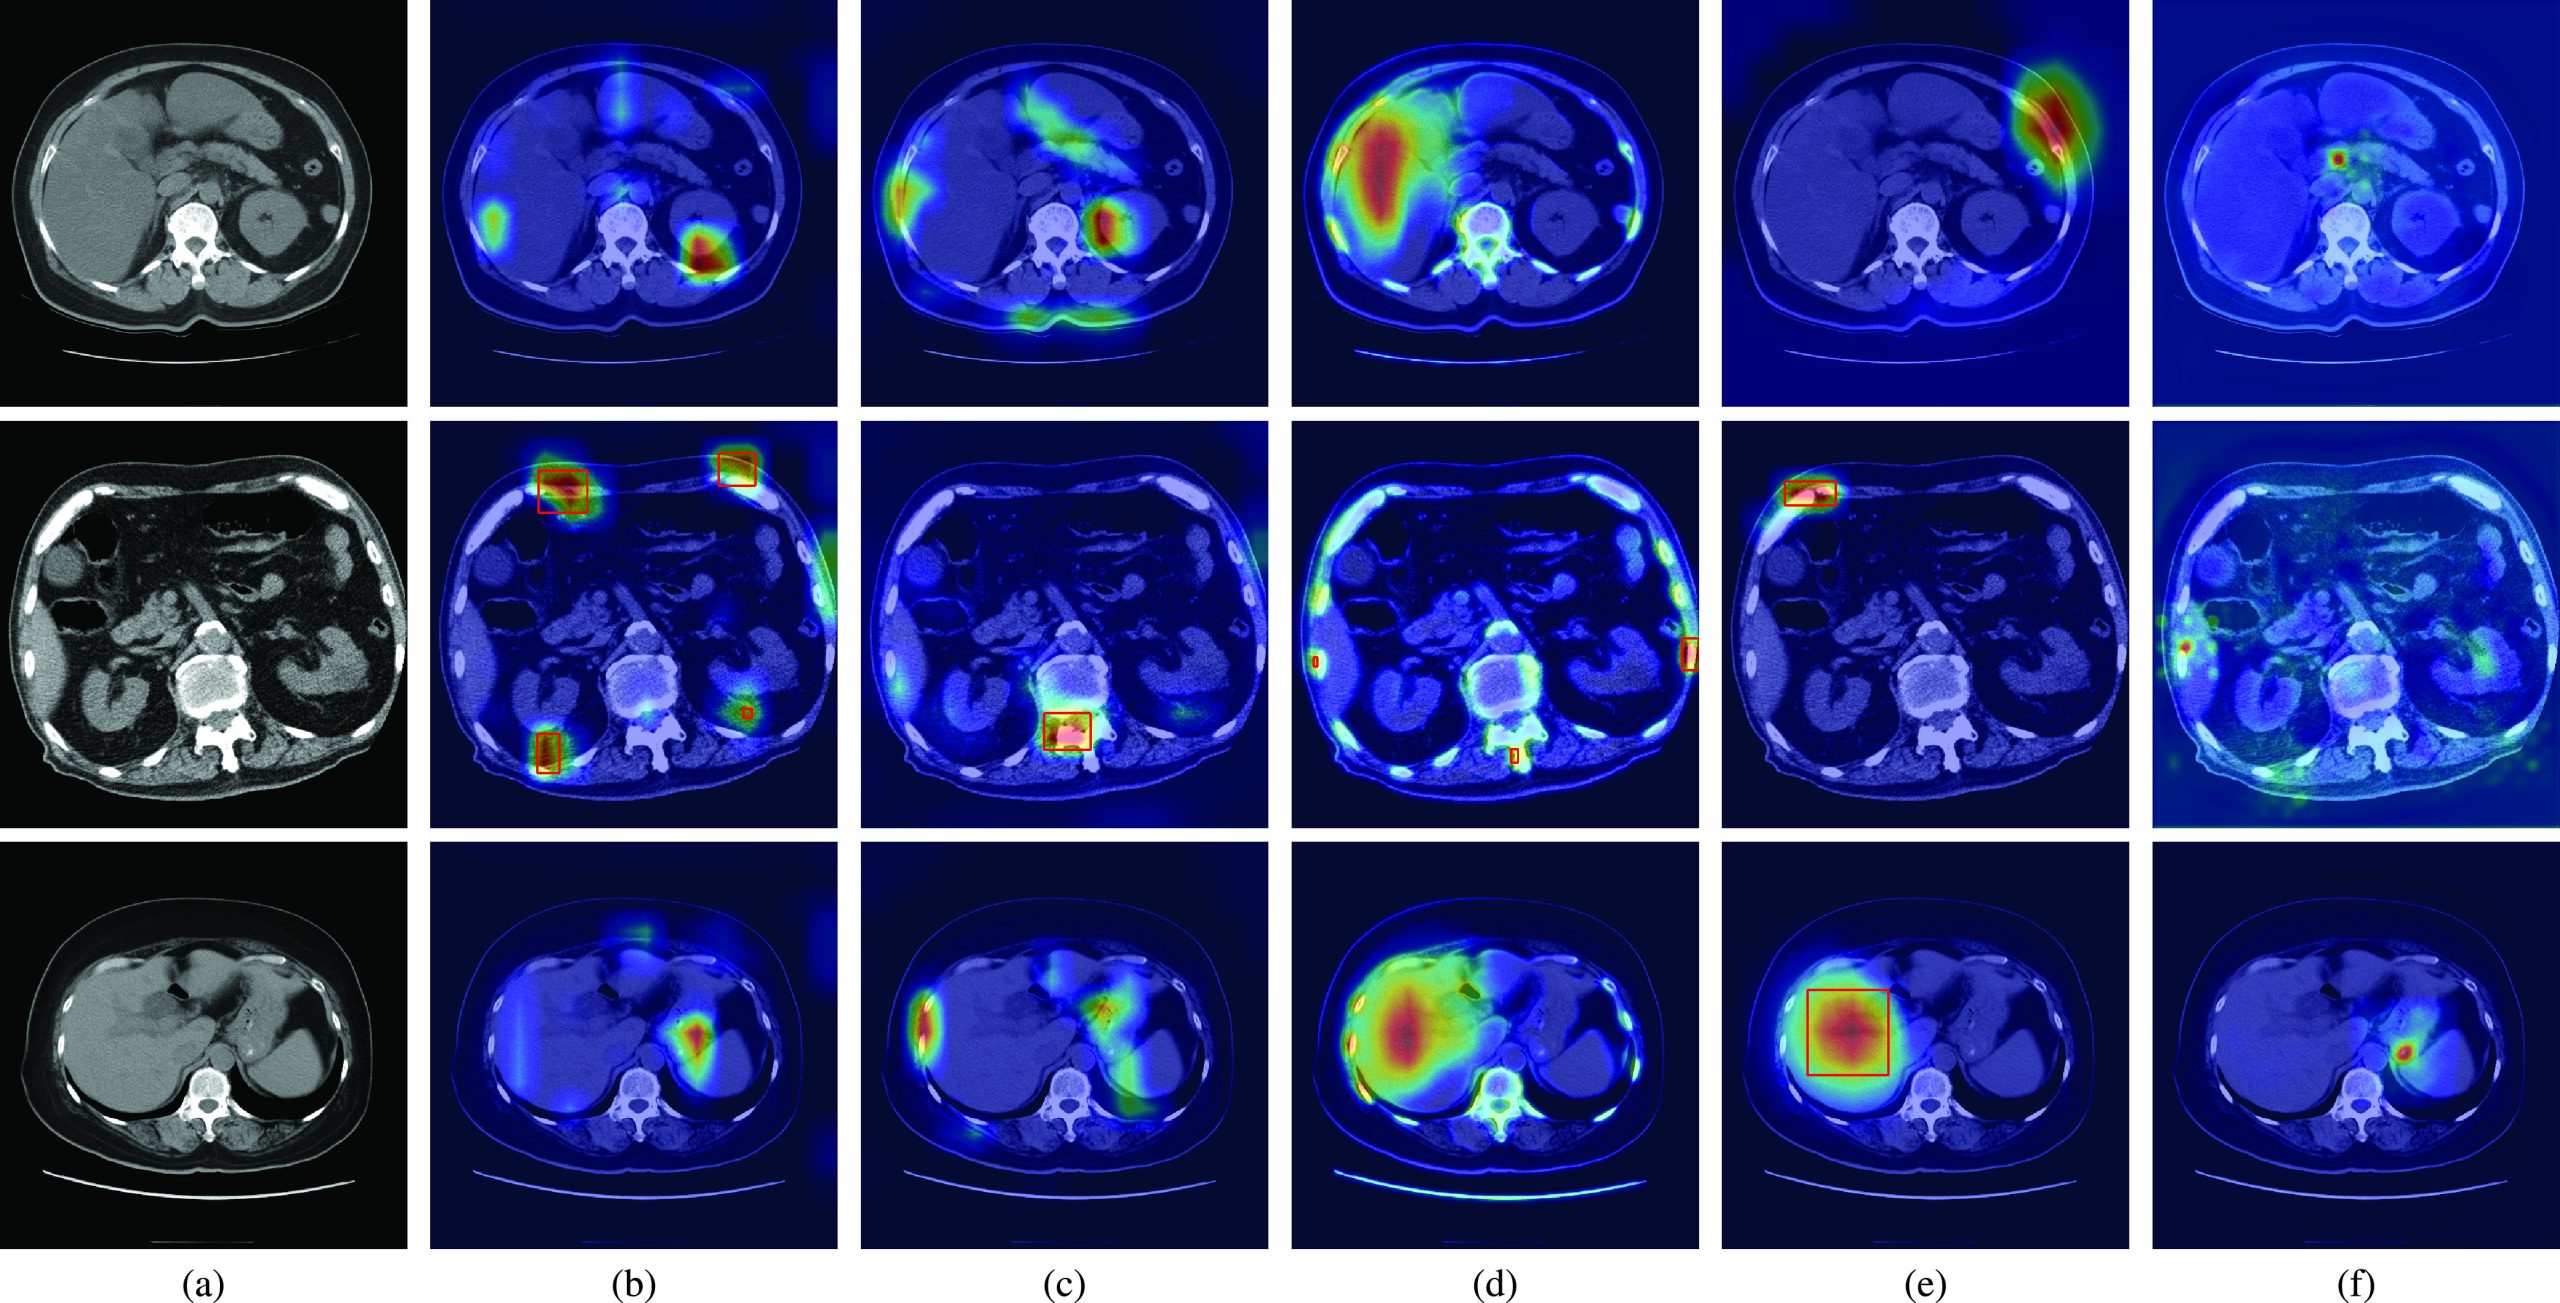

Fig. 2 shows the qualitative results of the state-of-the-art methods and the proposed method for normal CT scans of three patients. The attention maps of each method are also shown in Fig. 2. The red rectangles show the CBD stone detection results when the method incorrectly classifies the normal CT scans as the abnormal CT scans with CBD stones. Fig. 2(a) shows the ground truth of normal CT scans. The results of CAM are shown in Fig. 2(b). Because CAM considers the feature responses after global average pooling, the learned features then easily focus on bone and angiosteosis regions which are salient compared with other organs in the CT scans. Similar results can also be observed in Grad-CAM as shown in Fig. 2(c). As a result, the false detection and false classification results of CAM and Grad-CAM are observed from the CT scan of the second patient.

Compared with CAM and Grad-CAM, MS-CAM considers the scale information with the attention mechanism of the fully connected operations. It can then observe liver regions as shown in the CT scans of the first and third patients of Fig. 2(d). Nevertheless, MS-CAM still incorrectly detects CBD stones for the second patient due to the salient features of bones. As indicated by SPA, these CAM based methods easily miss object structure information because extremely high feature responses are considered. To solve the problem, a restricted activation module is proposed in SPA. Nevertheless, extremely high feature responses such as bone and liver regions still affect the classification results of SPA for the second and third patients as shown in Fig. 2(e). Thus, SPA also incorrectly locates the bone and liver regions as CBD stones. Fig. 2(f) shows the results of the proposed method. With the foreground loss, background loss and consistency loss, the learned attention maps focus on the regions which can distinguish CBD stones from ambiguous regions such as bone regions of the second patient and angiosteosis regions of the third patient. Thus, the proposed method can successfully classify these CT scans as normal CT scans based on the learned features.